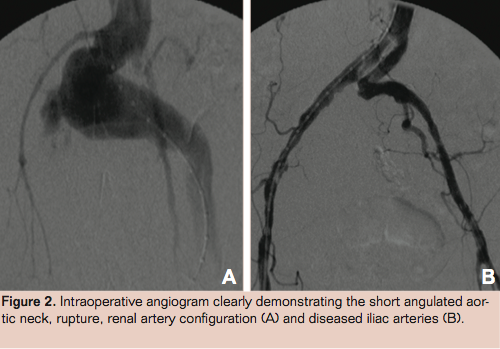

This maneuver effectively plicated the infrarenal neck and excluded blood flow from the sac. Aortography was performed to confirm the endoleak resolution and perfusion of the adjacent renal arteries (Figure 5) before a mass wound closure was performed and the patient was transferred to the intensive care unit for ongoing resuscitation, correction of coagulopathy, and warming.

Periaortic banding is a technique that has been described in the elective treatment of type 1A endoleak.17-19 It involves a limited laparotomy and careful dissection around the aorta immediately below the renal arteries. In the rupture setting, care must be taken to avoid any retroperitoneal hematoma so as not to exacerbate bleeding. A large right-angle clamp can be passed around the aortic neck taking care to avoid injury to adjacent structures, particularly the renal arteries, veins, and lumbar vessels. Once around the aorta nylon tapes can be tied to snug and seal the aortic wall against the stent graft. Care must be taken to avoid over tightening which may result in stent-graft collapse and involution. The length of aortic neck will determine how many tapes can be accommodated. Normally the placement of 2 to 3 is possible and sufficient to provide a seal. The femoral access sheaths are left in place and final angiography performed to confirm flow through the aortic graft, renal arteries, and the resolution of endoleak (Figure 5). If there is suspicion of bowel ischemia or compartment syndrome, the abdominal cavity may be left open to facilitate a second look laparotomy as well as decompress.